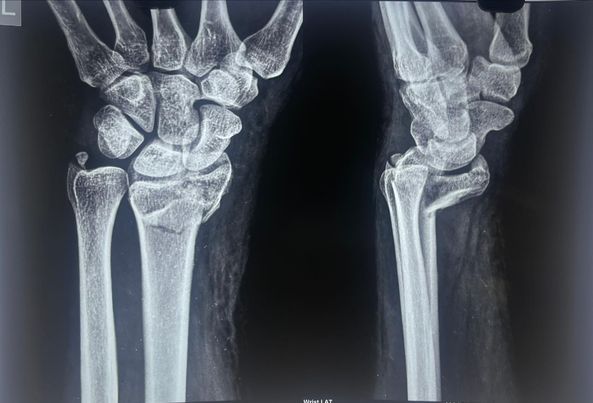

68 year old man ACL (anterior cruciate ligament) reconstruction of Knee

There used to be a common consensus that ACL reconstruction of knee should not be done in old age, this idea has now largely been debunked with statistical evidence. this 68 year old man with a traumatic anterior cruciate ligament tear had intact lateral and medial meniscus and quite normal cartilage in the weight bearing […]